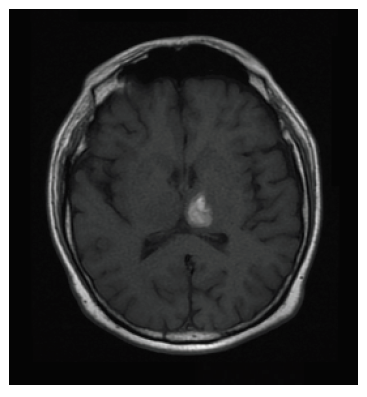

Se reporta ecografía de vasos carotideos sin compromiso hemodinámico cerebral. La RMN evidenció hematoma intraparenquimatoso de ubicación talámico-izquierda (figura 2). La panangiografía cerebral no reveló hallazgos patológicos. Se decide un tratamiento conservador y monitorización neurológica. Transcurrido el tercer día de hospitalización, el paciente recuperó la totalidad de sus funciones neuropsicológicas sin secuelas. Durante los siguientes tres días de hospitalización el paciente continuó su evolución de manera satisfactoria. Se dio de alta médica con recomendaciones y manejo sintomático. No obstante, continúa en seguimiento periódico por parte del Departamento de Neurología.